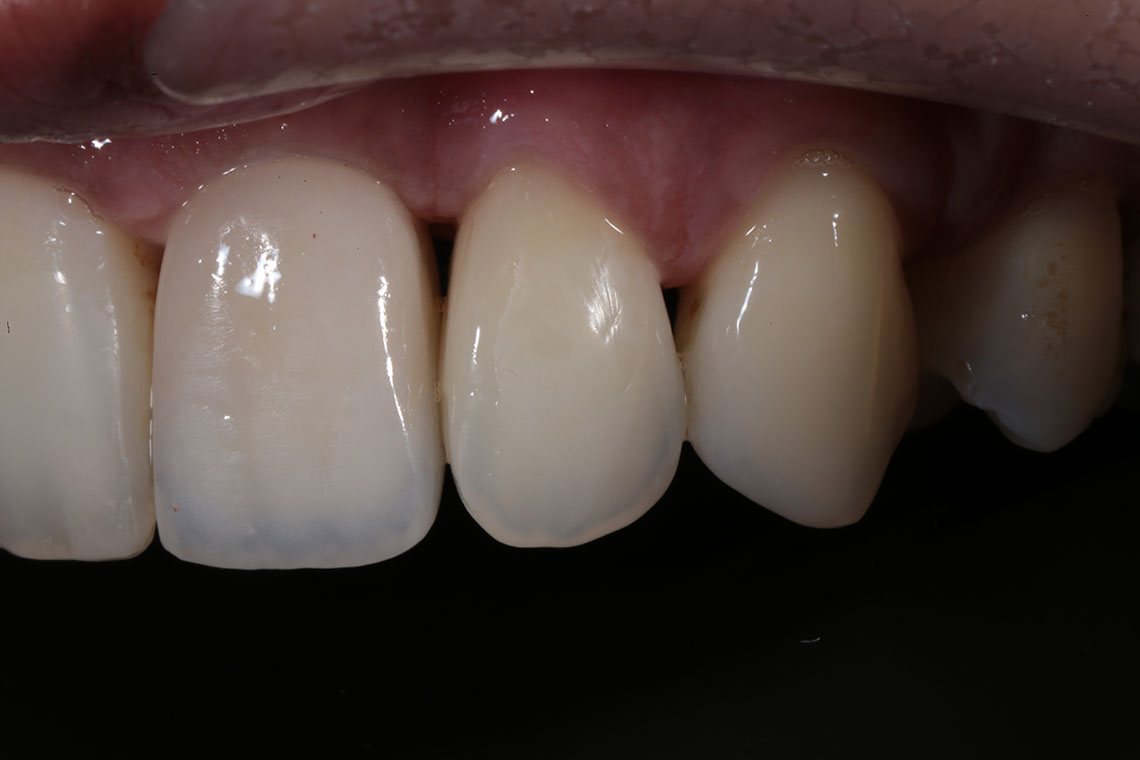

This lovely lady attended with very low confidence due to her teeth and smile. Gum disease and trauma had led to the teeth drifting. One of her front teeth was so loose that it needed to be replaced. We started by providing intensive treatment with our dental hygienist to treat the gum disease. Following this Invisalign® braces were used to align the teeth and the teeth were whitened. A dental implant was then placed to replace the loose front tooth and composite bonding was performed to the adjacent front tooth. The change in the patient’s confidence as a result of this work was breathtaking.